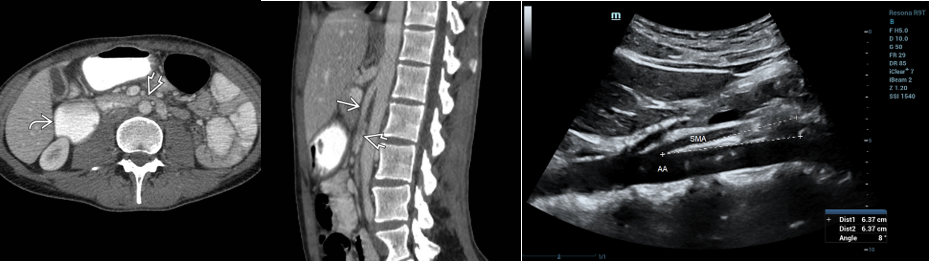

• 정의: 십이지장 3rd portion이 대동맥과 SMA 사이에 눌려서 발생

• 진단

• 상부 위장관 조영검사

• 영상 소견